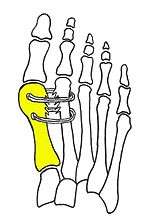

Surgical principle and technique of the syndesmosis procedure

Syndesmosis procedure addresses specifically the two fundamental problems of metatarsus primus varus deformity that gives rise to the bunion deformity. They are leaning and instability of the first metatarsal bone . Syndesmosis procedure uprights the leaning first metatarsal bone with strong binding sutures between it and the second metatarsal bone (Fig. 2) and then also stabilizes it uniquely by creating a fibrous connecting bridge between these two bones (Fig. 3,4). First metatarsal bone can be readily realigned is because by definition of the metatarsus primus varus deformity its first metatarsal is abnormally loose and mobile.